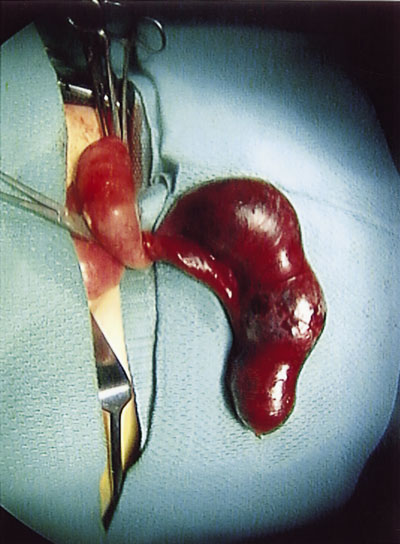

Surgical exploration via the standard McBurney incision revealed a dilated gangrenous appendix twisted 360 degrees anticlockwise at its base, as shown in the operative photograph.

Histopathological examination of the appendix revealed a cystadenoma close to its distal end.